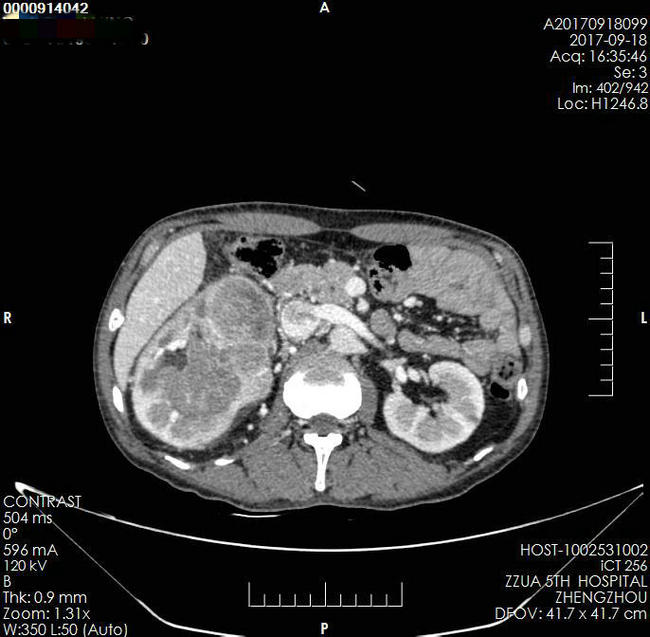

▲ 术前影像资料

患者,男,49岁,发现腹腔巨大占位1月余入院。平素患者无特殊不适,既往史、家族史无特殊。近1月来消瘦,曾辗转就诊省内三家三级医院,建议放弃手术。入院诊断:右肾巨大肿瘤并下腔静脉癌栓Mayo Ⅲ级(癌栓远端达第二肝门水平)。